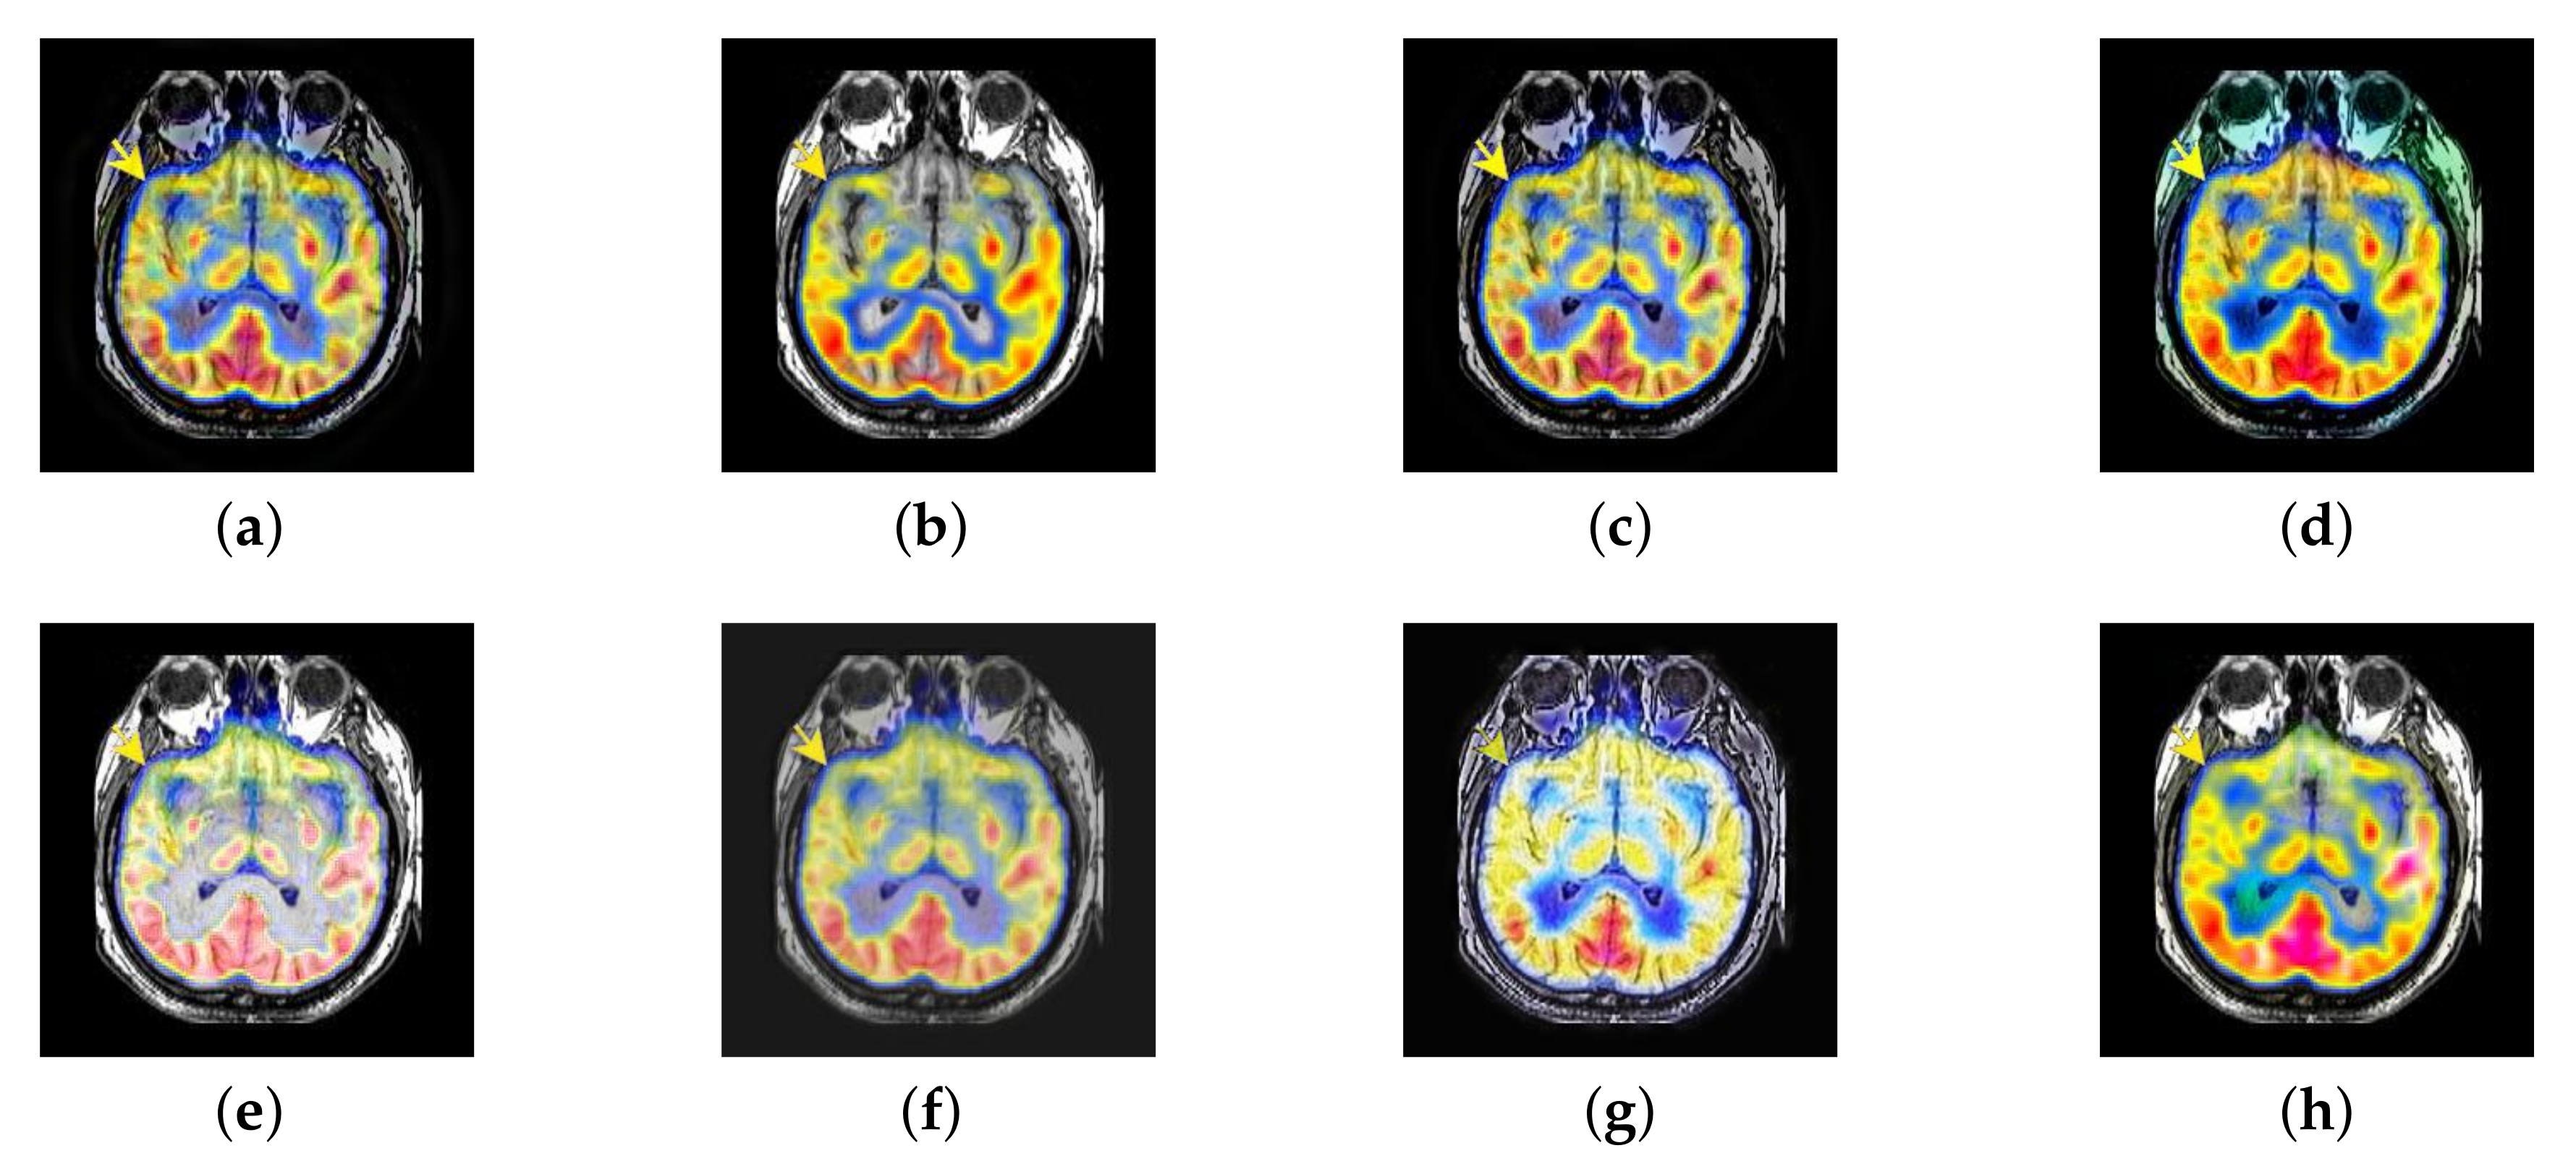

In this section, there are four multi-modal image sets and each set is consist of MRI image and SPECT image that are corresponding to the sanme location slice of the brain as shown in Figure 7. Among them, Figure 7e,f are captured from patients who have suffered a subacute stroke. Figure 7a–d,g,h are captured from patients who have brain tumor. The fused images with different fusion methods based on DTCWT, NSCT, GFF, LPSR, IGM, DDcGAN, FusionCNN, and the proposed methods are shown in Figure 8, Figure 9, Figure 10 and Figure 11. It can be seen that the fused images obtained by LPSR and FusionCNN algorithm have serious color distortion. Based on DTCWT and NSCT algorithm, the fusion image structure information is not obvious. The fused images obtained by GFF and IGM algorithm contain almost no color information, which is not conducive for doctors to make correct diagnosis. The image obtained by the DDcGAN algorithm saves the color information in the SPECT to a great extent; however, the brightness of the fused image is too large, which causes the image to have no sense of hierarchy and the contrast to decrease. By comparing with other algorithms, we find that our algorithm has good color retention effect, clear structure information, moderate brightness, and no artifacts.

Figure 7.

Four pairs of magnetic resonance imaging (MRI)-single-photon emission computed tomography (SPECT) source images: (a,c,e,g) are MRI images; (b,d,f,h) are SPECT images.

Figure 8.

Fused medical images obtained by different algorithms (Figure 7a,b): (a) dual tree complex wavelet transform (DTCWT), (b) guided filtering fusion (GFF), (c) non-subsampled contourlet transform (NSCT), (d) Laplacian pyramid sparse representation (LPSR), (e) internal generative mechanism (IGM), (f) Fusion convolutional neural network based (FusionCNN), (g) dual-discriminator conditional generative adversarial network based (DDcGAN), and (h) FusionNet.